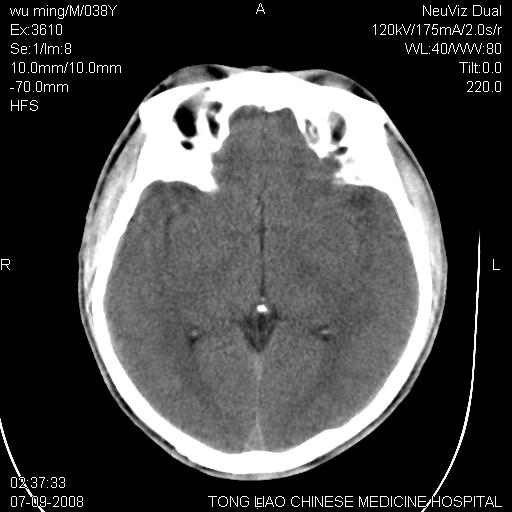

标题: CT14544:患者5楼坠下15分钟后CT扫描,2小时后死亡,请战友指 [打印本页]

标题: CT14544:患者5楼坠下15分钟后CT扫描,2小时后死亡,请战友指

考虑:面骨、颅底骨多发骨折,颅内高压(脑肿胀)。

面骨、颅底骨多发骨折,右侧硬膜下小血肿,弥漫轴索损伤,死亡原因可能是多种因素致。

1)颅底骨及颌面骨多发性骨折。2)副鼻窦及双侧鼻腔积血。

颅底骨折,窦腔内积血。考虑死亡原因为脑水肿压迫脑干或因大量失血死亡。

前颅窝颅底骨折,死的原因应该从头部来看不用说就是重度颅脑损伤。